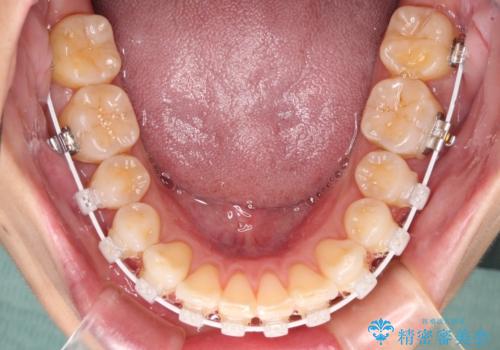

- 矯正装置

- 審美装置

横顔の印象から、抜歯をして積極的に口元を引っ込める必要はなかったため、アンカースクリューを用いて上顎歯列全体を後方に移動させることとしました。